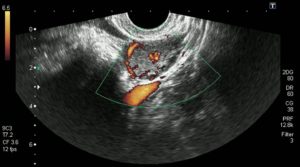

Хорошо известно, что ультразвук способен вызывать тепловые и нетепловые (механические) биоэффекты, поэтому для минимизации риска рекомендовано проводить исследование для 1-го триместра только в защищенном режиме — не выходя за рамки диапазона 3–4 мГц, продолжительность исследования должна быть минимально возможной, использование энергетического доплера нежелательно.

- Трансвагинальное. Самая точная методика обследования, используемая на ранних сроках вынашивания ребенка. С помощью этой методики определить беременность можно уже спустя 3 недели со дня предполагаемого зачатия. Наряду с обследованием необходимо сдать анализ крови на определение уровня ХГЧ. И если наблюдается динамика роста гормона, но во время УЗИ не было обнаружено плодное яйцо, то речь может идти о внематочной беременности.

Ультразвук способен точно определить беременность тогда, когда уровень ХГЧ (хорионического гонадотропина) в крови женщины превысит тысячу единиц.

В этом случае врач уже способен увидеть в полости матки плодное яйцо (при многоплодной беременности – два или три плодных яйца).